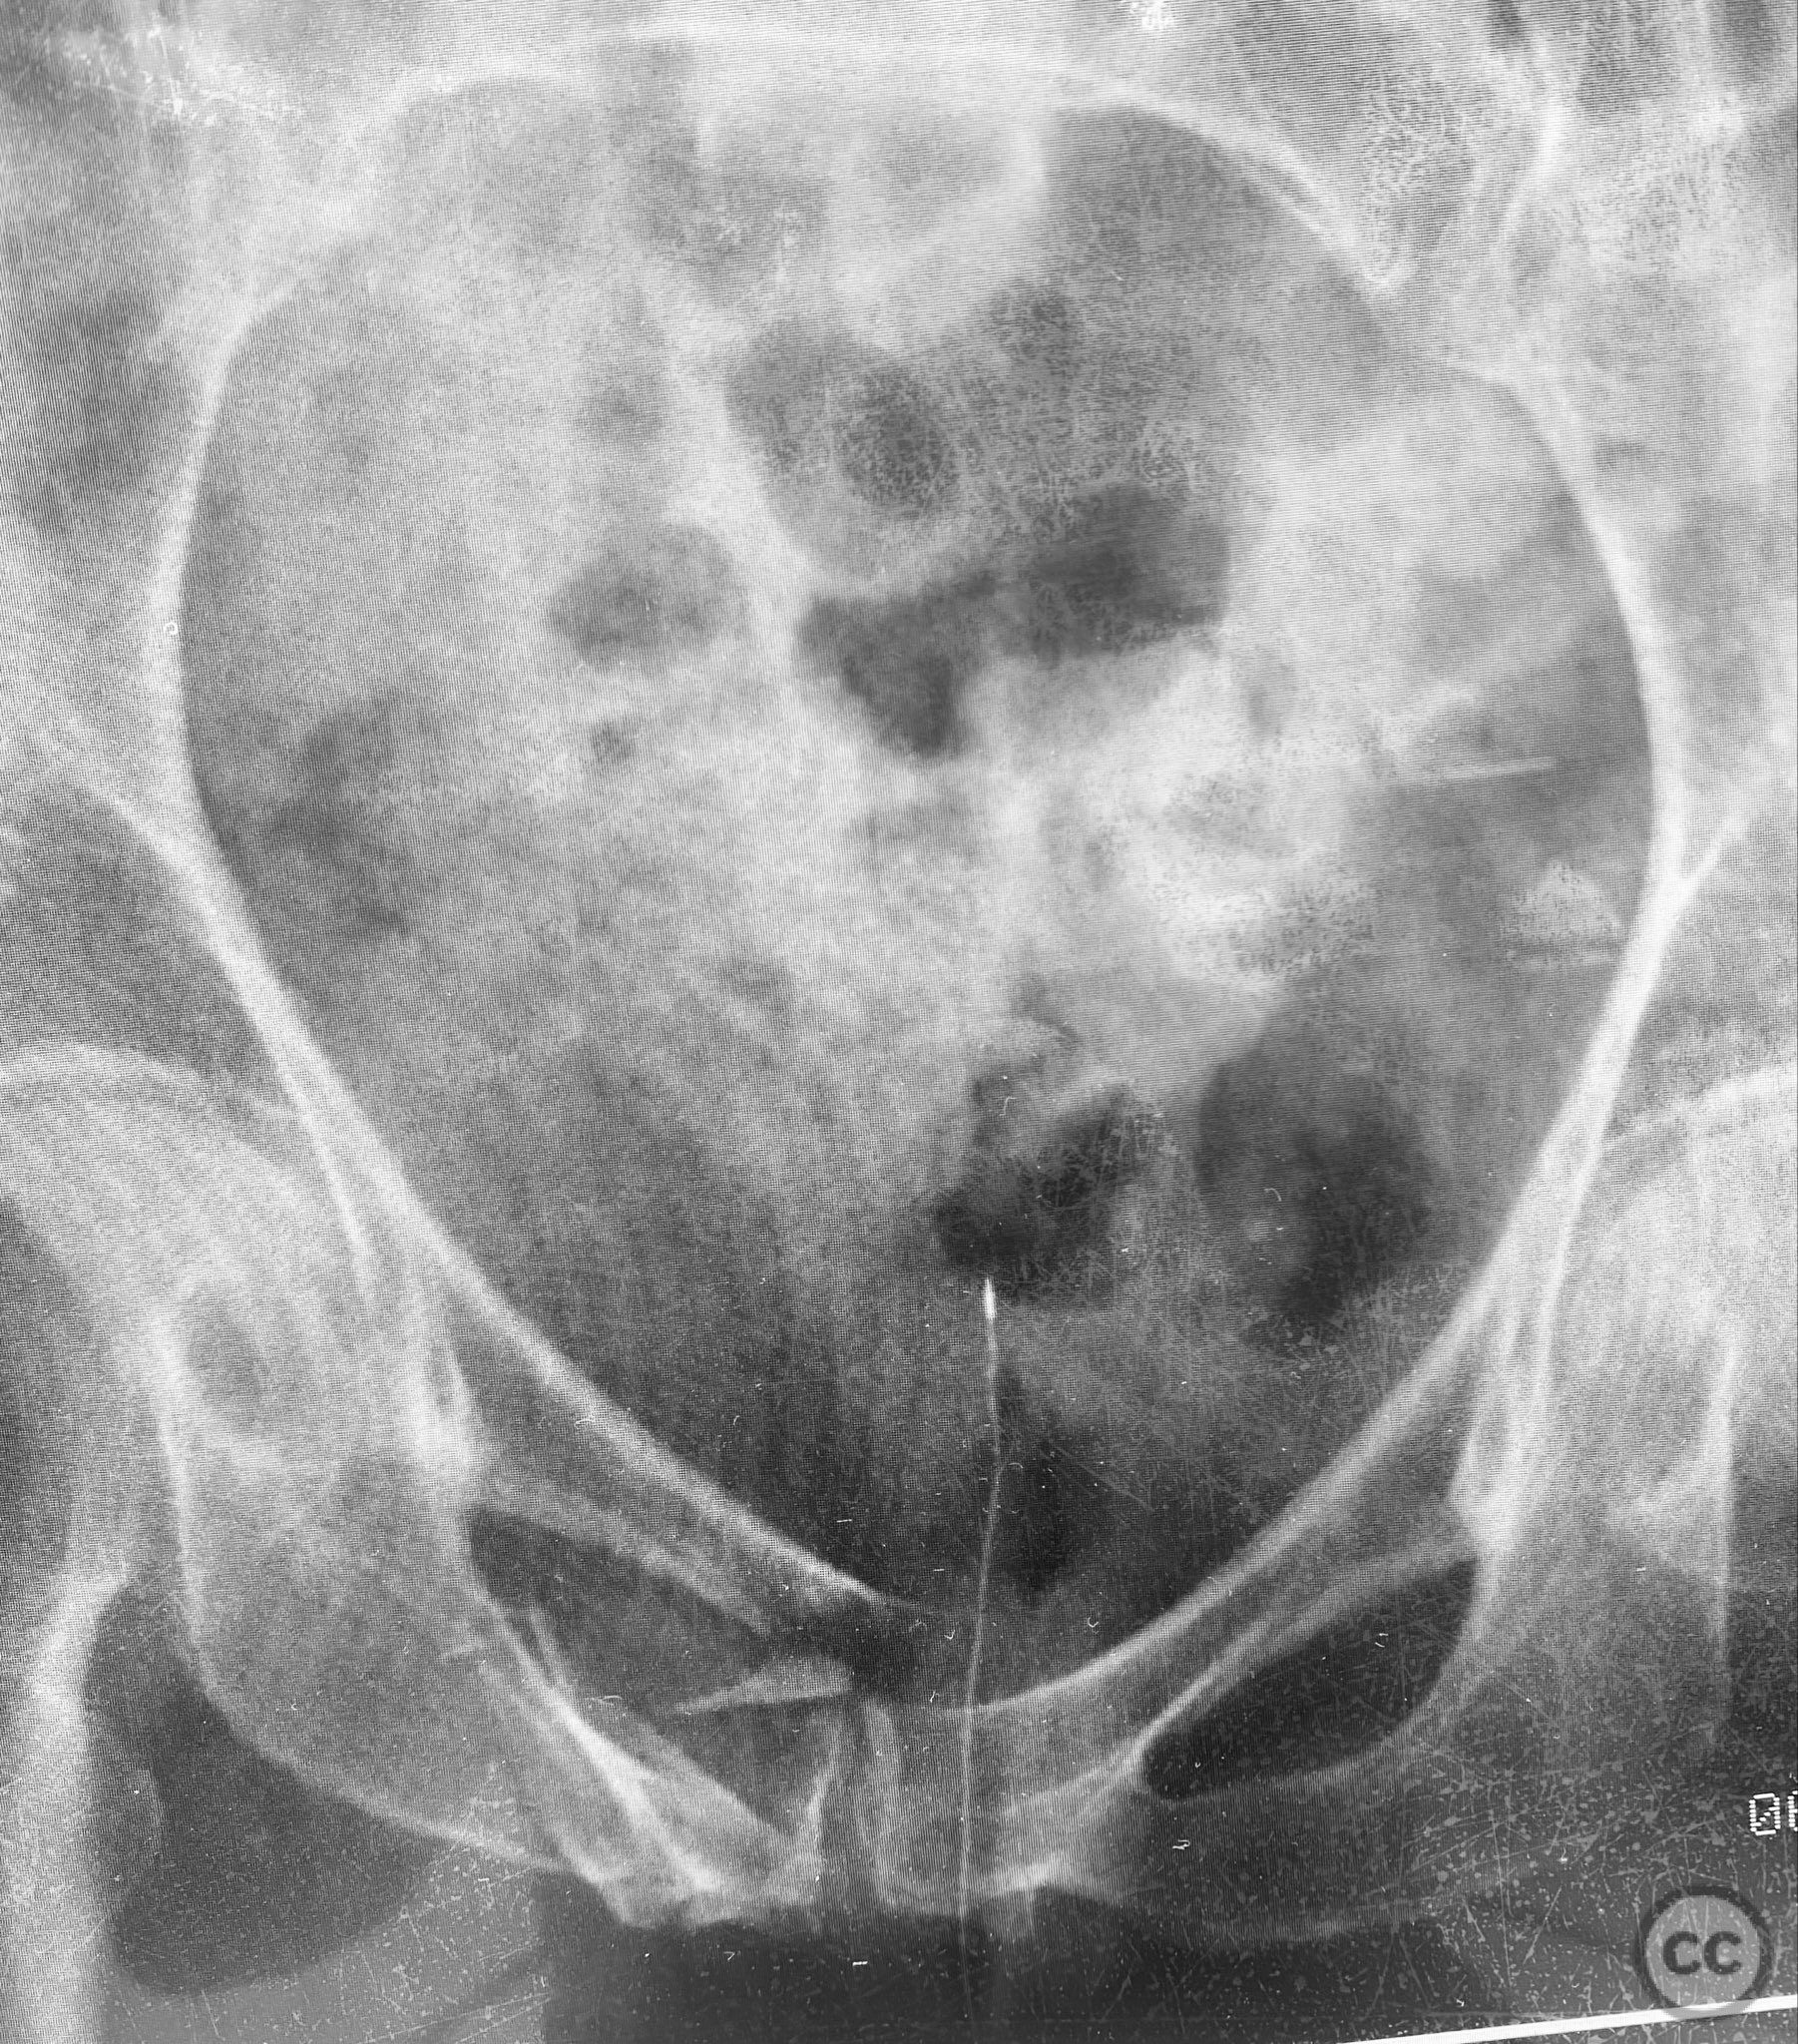

Pelvic Ring - AO/OTA 61x

Pelvis - AO/OTA 6x